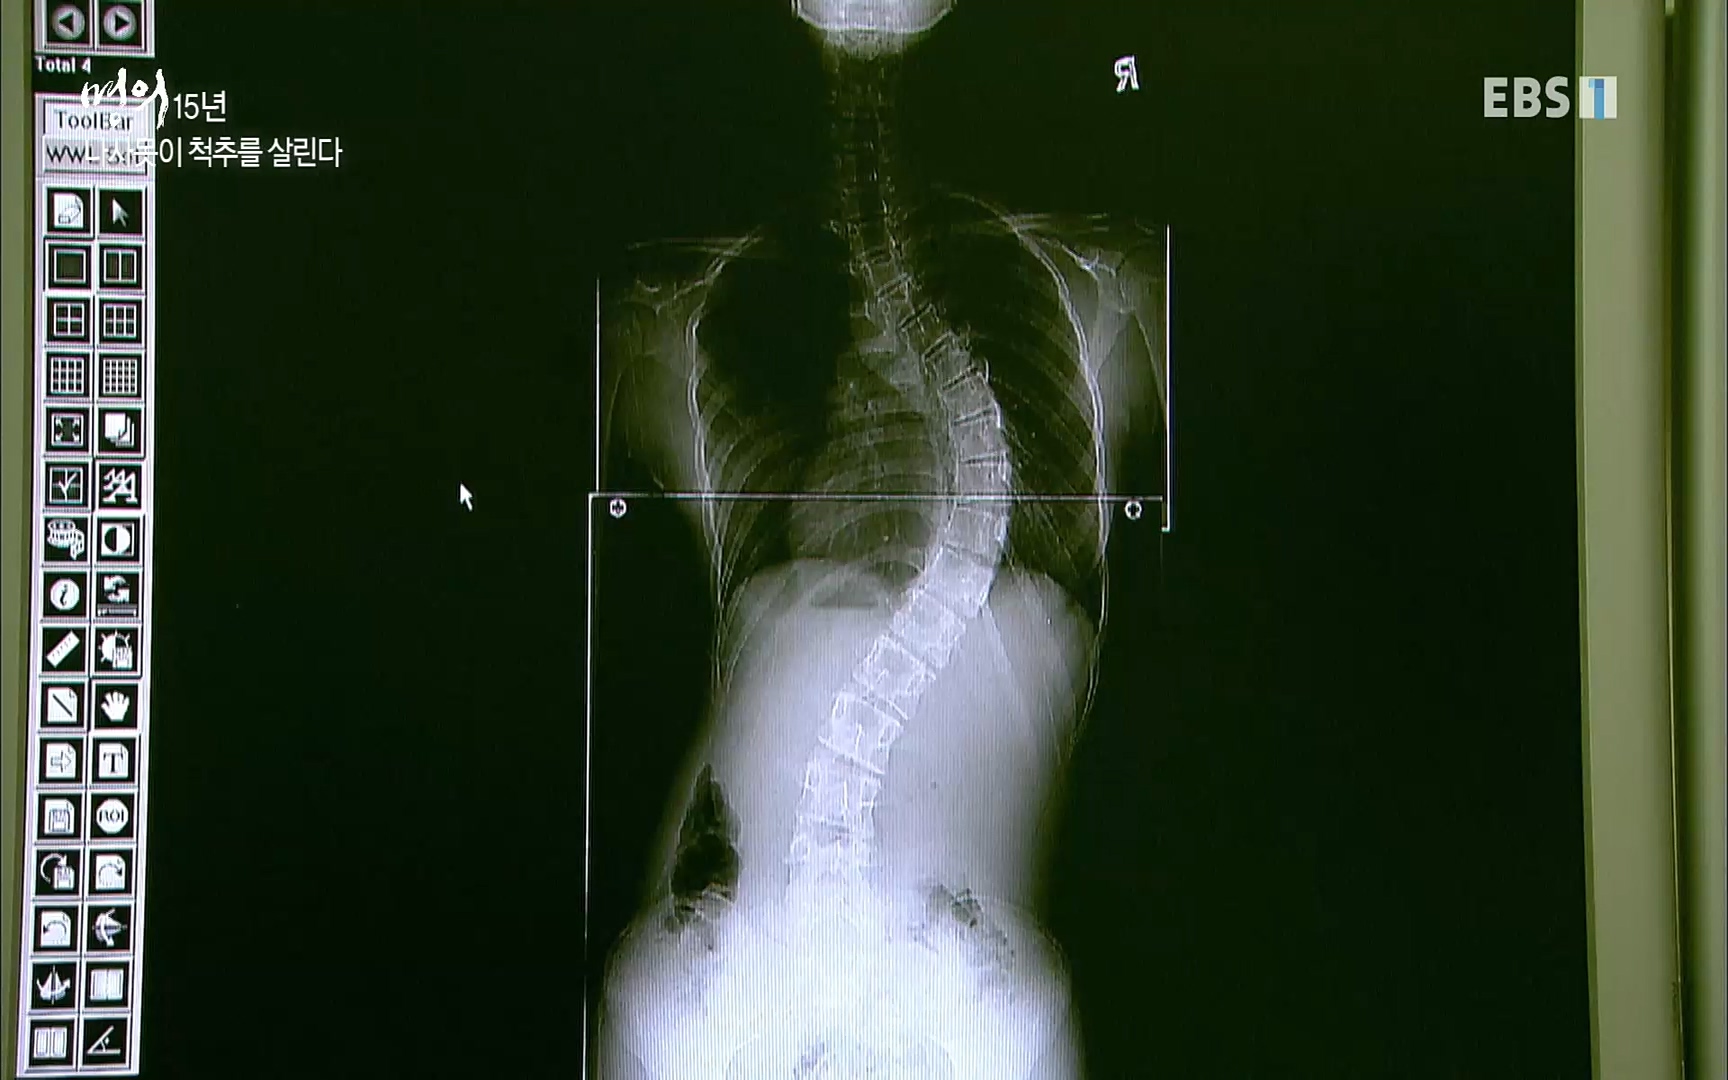

석세일 명예교수 정형외과 전문의 ·1995년 세계 최초 측만증에 척추경 나사못삽입술 시도 ㆍ척추변형에 대한 척추 후방 절제술, 척추 회전술 개발